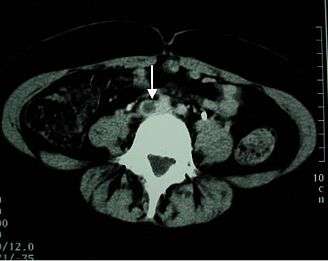

Imaging tests of the veins are used in the diagnosis of DVT, most commonly either proximal compression ultrasound or whole-leg ultrasound. Each technique has drawbacks: a single proximal scan may miss a distal DVT, while whole-leg scanning can lead to distal DVT overtreatment.[3] Doppler ultrasound,[58] CT scan venography, MRI venography, or MRI of the thrombus are also possibilities.[3][56]